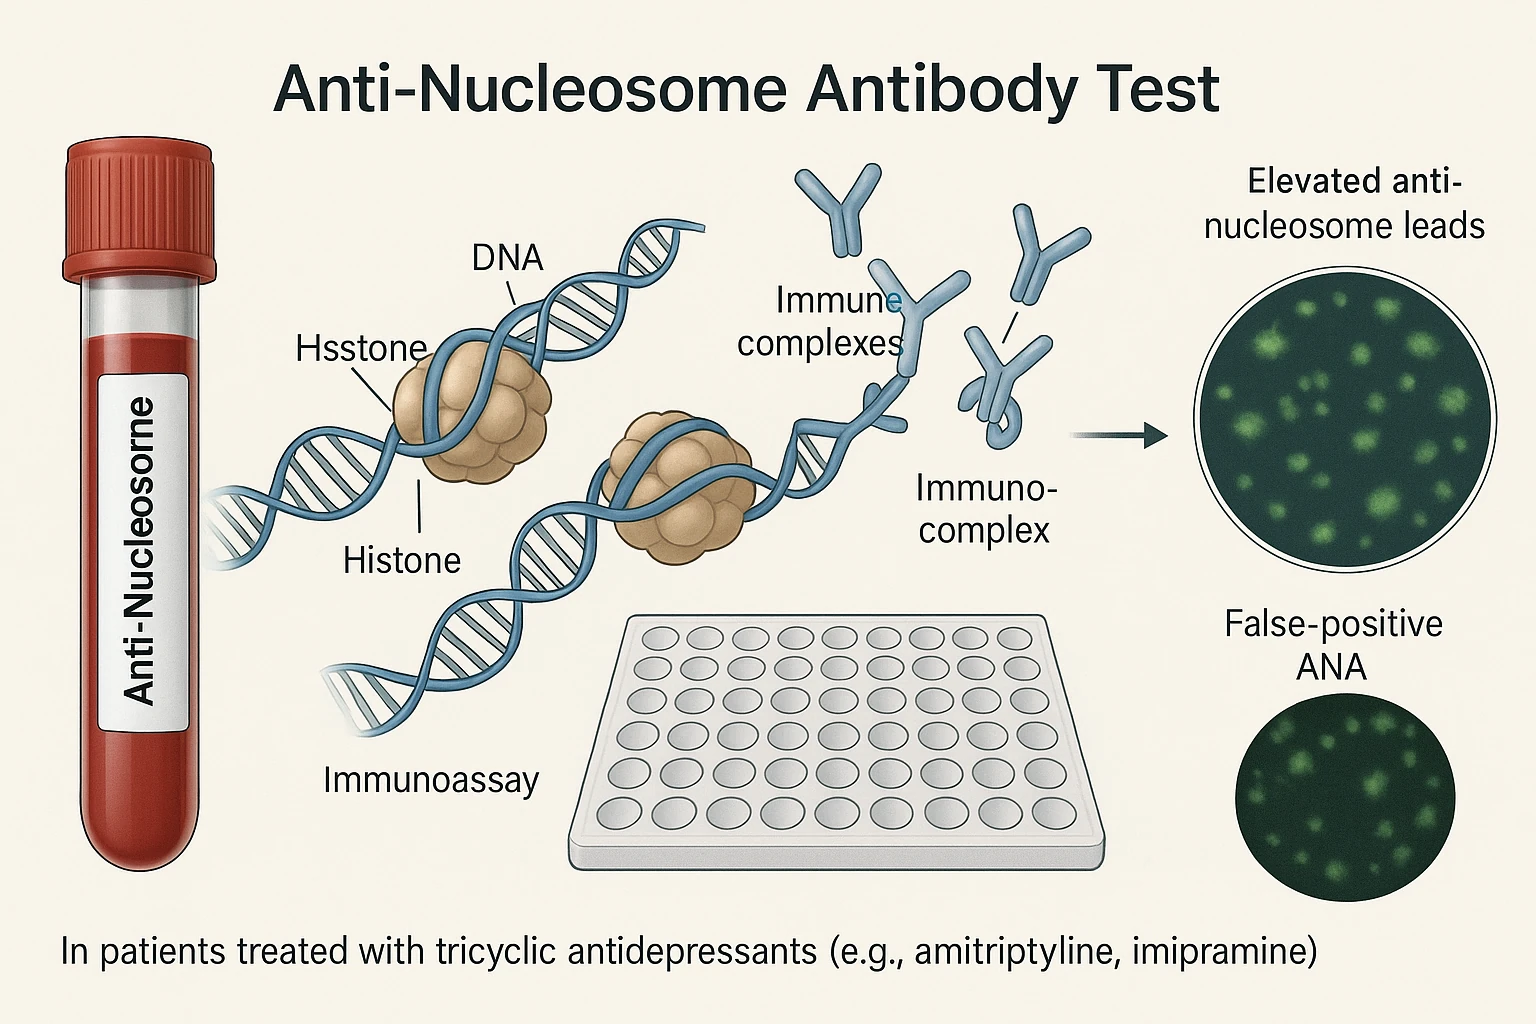

مکانیسم احتمالی:

– تغییر ساختار آنتیژنهای سلولی در اثر متابولیت دارو

– تشکیل کمپلکسهای ایمنی در بافتهای عصبی و اندوتلیال

– تحریک سلولهای T و B و تولید آنتیبادیهای ضد هیستون و ANA

در چنین حالتهایی، حرکت بیمار نه فقط به دلیل بلوک دوپامینی، بلکه به واسطه التهاب خودایمنی خفیف در سیستم عصبی مرکزی تشدید میشود.